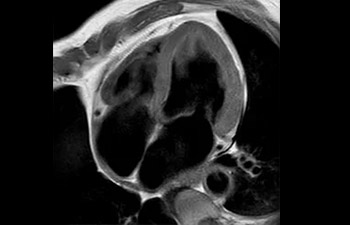

Columna.

Estenosis de la columna lumbar

con Compressed SENSE